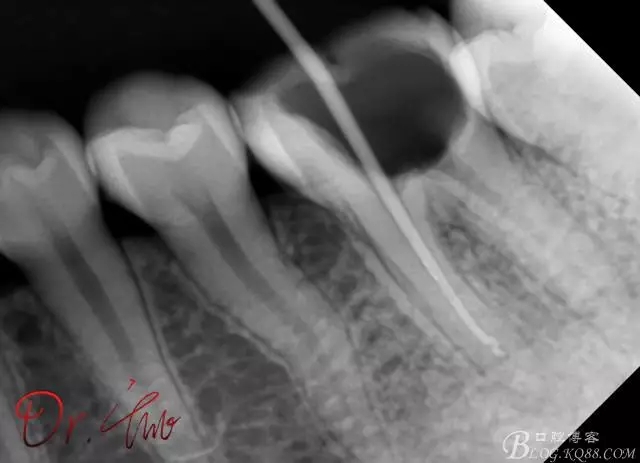

第一次試主尖

640.webp (2).jpg